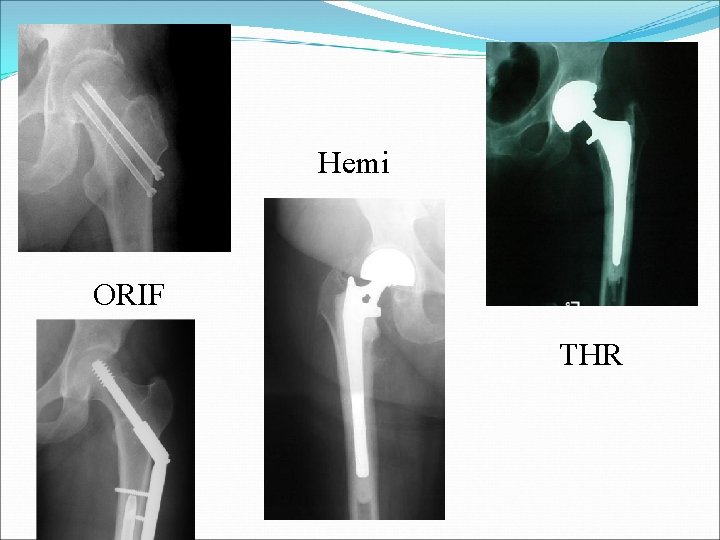

Femoral Neck Fractures Treatment Options Operative ORIF Hemiarthroplasty (Endoprosthesis) Total Hip Replacement

Femoral Neck Fractures Young Patients Urgent ORIF (<6 hrs) Elderly Patients ORIF possible (higher risk AVN, non-union, and failure of fixation) Hemiarthroplasty Total Hip Replacement

Hemi ORIF THR